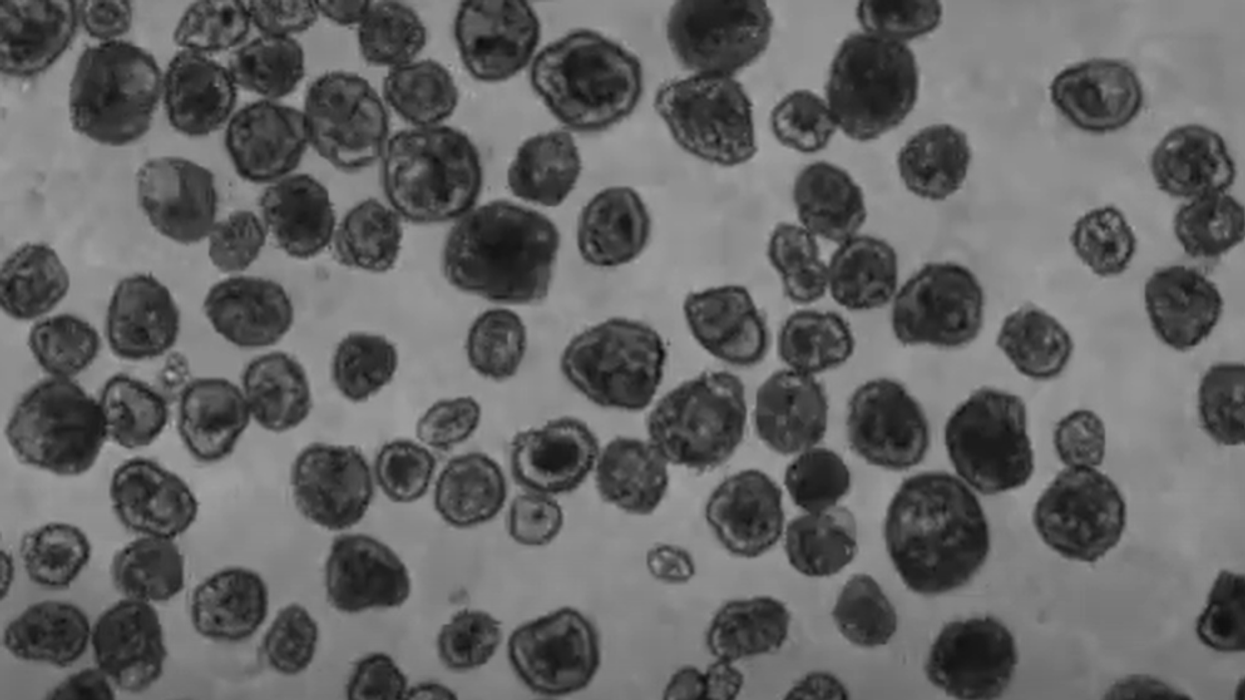

Robotët e vegjël, të emëruar si antrobotë, janë krijuar nga qelizat e trakesë së njeriut, të marra nga donatorë anonimë të moshave dhe gjinive të ndryshme.

Shkencëtarët e përdorën qelizën trakeale, për shkak të funksionit të saj që ka për të vënë grimcat në kanalet e frymëmarrjes në lëvizje, në mënyrë që të inkurajojë edhe lëvizjet e antrobotëve.

Ndryshe, antrobotët kanë mbijetuar deri në 60 ditë në kushte laboratorike.